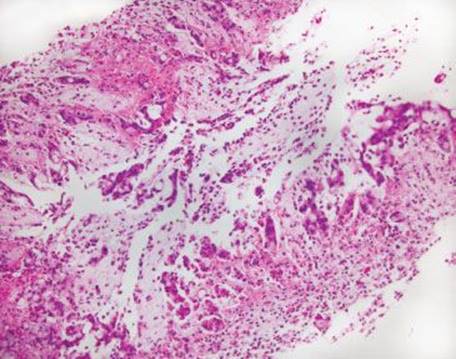

Figure 4.272 Endometriosis. Higher power shows convoluted glands surrounded by a cuff of stroma cells and intermixed lymphoid cells.

Figure 4.273 Endometriosis. Higher power of previous image. Cilia are not definitively identified in this suboptimal specimen. Biopsies of the lesion had raised concerns for an infiltrating adenocarcinoma because the glandular elements were not recognized as endometrial, the overlying reactive changes were interpreted as dysplasia, and numerous mitotic figures were seen.